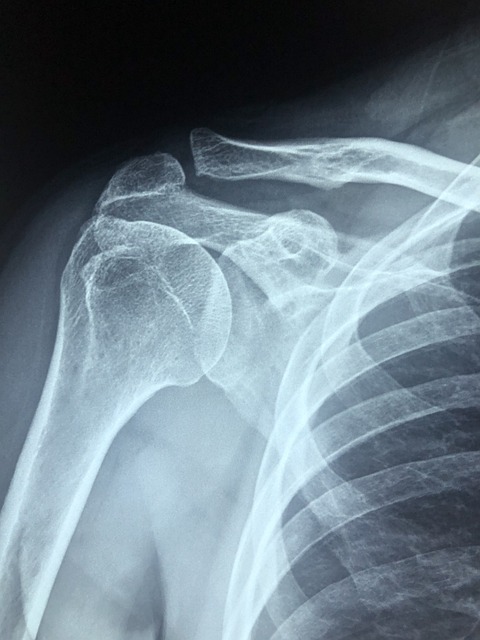

흔히 오십견이라고 알고 있는 질병은 의학적으로 '유착성 관절낭염'으로 불리며, 어깨 관절 주위의 조직이 염증과 함께 굳어지면서 발생합니다. 발병 초기에는 오십견의 증상이 미미할 수 있지만, 점차적으로 어깨의 통증이 심해지고 어깨 관절의 움직임이 제한되며 일상생활에 큰 불편을 초래할 수 있습니다.